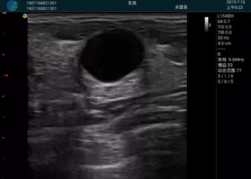

M20查看:囊內(nèi)回聲均勻,邊界清晰,囊壁光滑

M20引導抽吸術(shù)后囊腫消失,原區(qū)域空腔形成,脂肪層與腺體層架構(gòu)發(fā)生改變